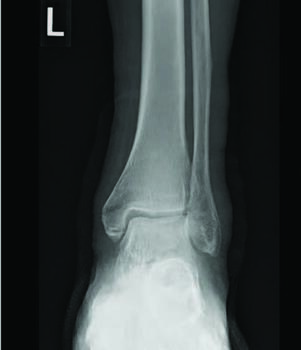

There are several studied and suggested surgical fixation options for treating complicated diabetic ankle fractures. As mentioned earlier, inappropriate treatment of these injuries can often lead to complications including the worst case scenario of Charcot arthropathy, and potential resultant limb loss. Hence, the common fundamental goals currently used for Charcot reconstruction also apply in ankle fracture fixation for patients with complicated diabetes.7 Specifically, these include obtaining a fixation construct with maximum rigidity and absolute stability, extending the fixation beyond the immediate zone of injury and planning incisions to minimize soft tissue trauma and optimize healing.4 Some fixation constructs suggested in recent literature include: circular external frame fixation; internal fixation using screws and plates; tibiotalocalcaneal (TTC) nail construct; and even locked fibular intramedullary nail fixation.4,8-10

Facaros and colleagues presented a case report of a patient with diabetes and neuropathy who sustained a displaced fibular fracture with significant joint subluxation and syndesmotic injury.11 Subsequent surgical intervention consisted of ORIF with plate fixation, multiple pro-syndesmotic screws and application of a multiplanar circular external fixator. This allowed a maximally stable and rigid construct and also allowed the patient to fully weight bear postoperatively on the external fixator. The patient underwent removal of the external fixator after 12 weeks without any long-term sequelae.11The use of multiple syndesmotic screws regardless of a syndesmotic injury is repeatedly suggested in the literature, as it allows for a more mechanically stable construct.4